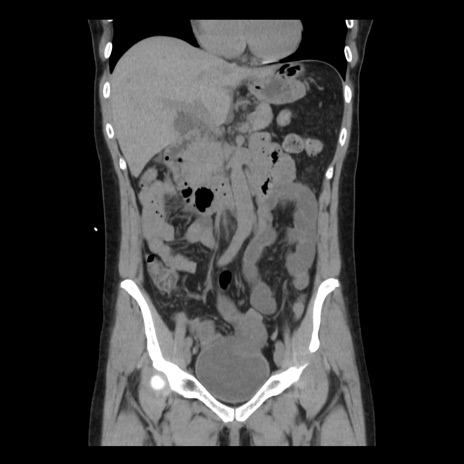

横断像